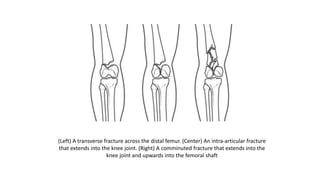

DESCRIPTION

• Distal femur fractures vary. The bone can break straight across (transverse

fracture) or into many pieces (comminuted fracture).

• Sometimes these fractures extend into the knee joint and separate the

surface of the bone into a few (or many) parts. These types of fractures are

called intra-articular. Because they damage the cartilage surface of the

bone, intra-articular fractures can be more difficult to treat.

(Left) A transverse fracture across the distal femur. (Center) An intra-articular fracture

that extends into the knee joint. (Right) A comminuted fracture that extends into the

knee joint and upwards into the femoral shaft